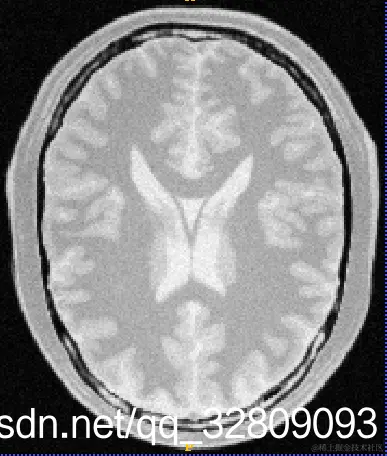

输入三维图像(BrainProtonDensity3Slices.mha):

切片1                                     切片2                                        切片3